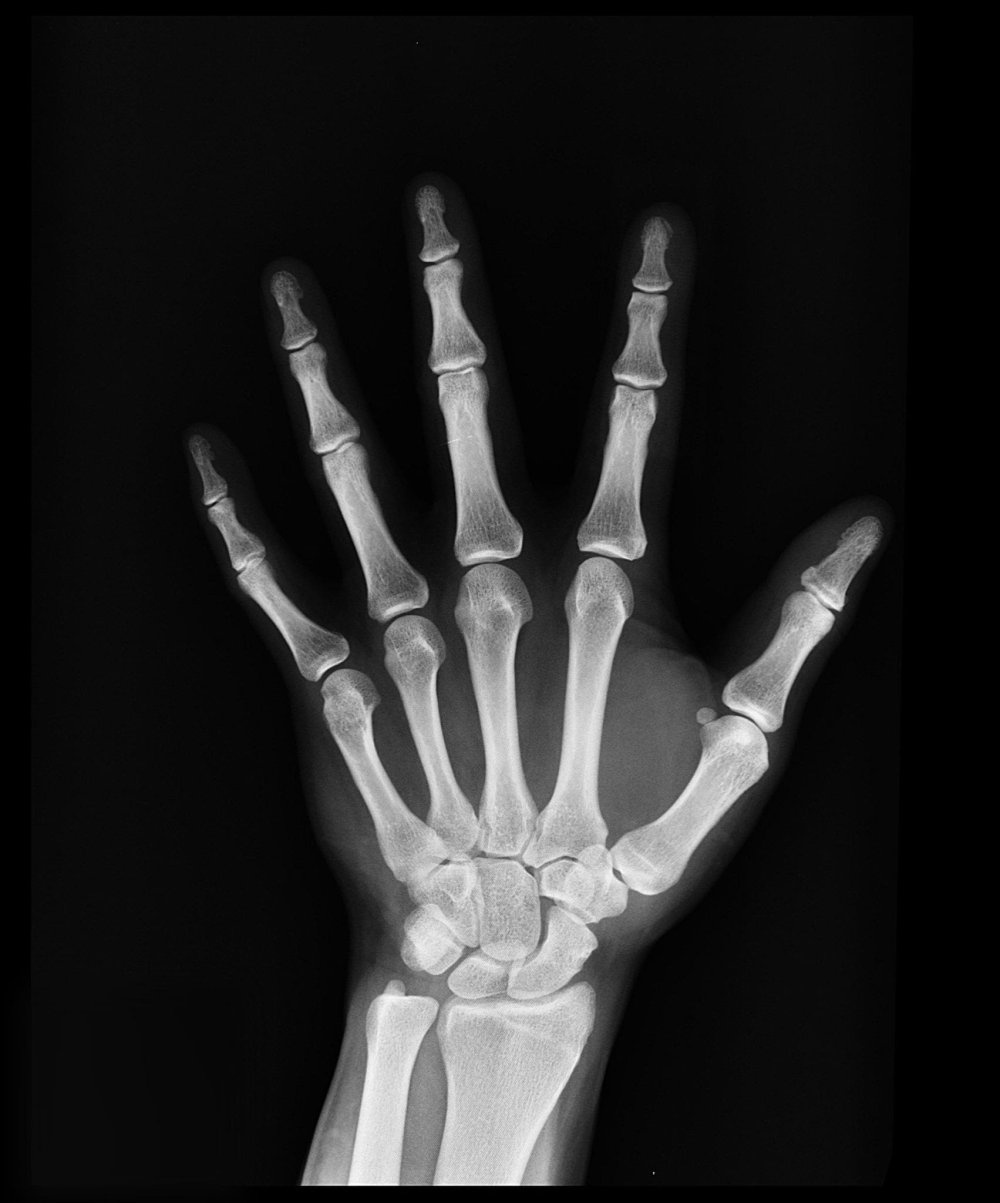

If these audible clicks, cracks or pops are painful on motion, then investigations are needed into whether there are bony changes or soft tissue changes that are causing the pain. MRIs can be helpful to analyse pathological changes to bone, cartilage, or other soft tissues. The other option is an X-ray, which can show any changes to joints, whether there is wear and tear, or a degenerative process that could be causing the joints to click, crack or pop due to the uneven surfaces and the grinding of the joints. A common pathology of this is arthritis which can be treated with regular manual therapy. This may, however, require an operative route depending on the condition and the chronicity. If not, then there are steroidal injections that may be preferable for inflammatory reduction and some pain relief. It should be noted though that this is only a short term relief of the problem and doesn’t help the root cause.